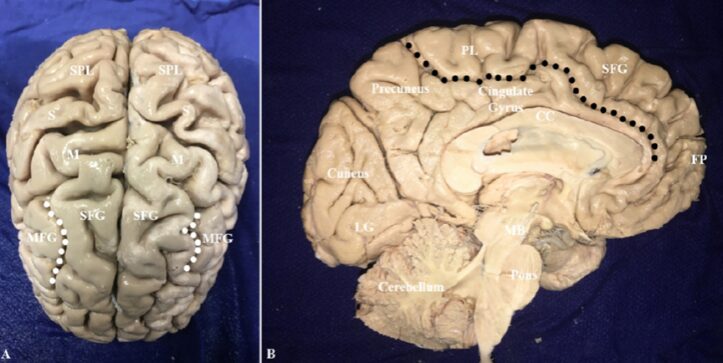

This study used diffusion spectrum imaging (DSI) data from 10 healthy adults’ brains from the Human Connectome Project to perform fiber bundle imaging, assessing the connections of the SFG with other brain regions as a whole. Based on the relationship between the white matter fiber bundles shown by DSI and surrounding important neuroanatomical structures, the study characterized the features of the SFG fiber bundles. All fiber bundles were located in the bilateral cerebral hemispheres, and their lateralization indices were calculated based on fiber bundle volumes. A modified Klingler technique was used for microscopic anatomical studies of 10 cadaver brains to determine the locations of the main connecting fiber bundles of the SFG. The researchers divided the cortical surface of the SFG into an upper lateral side and a medial side. The frontal pole is the anterior edge of the SFG, while the central sulcus and the paracentral lobule are the posterior edges of the SFG (Figure 1).

Figure 1. Anterior superior view (A) and mid-sagittal view (B) of the brain, showing parts of the frontal, parietal, and occipital lobes. In Figure A, the superior frontal sulcus is delineated by white dots; in Figure B, the cingulate sulcus is delineated by black dots; the lateral and medial sides of the SFG are clearly visible. CC: Corpus callosum; FP: Frontal pole; LG: Lingual gyrus; M: Motor center; MB: Midbrain; MFG: Middle frontal gyrus; PL: Paracentral lobule; S: Sensory center; SFG: Superior frontal gyrus; SPL: Superior parietal lobule.